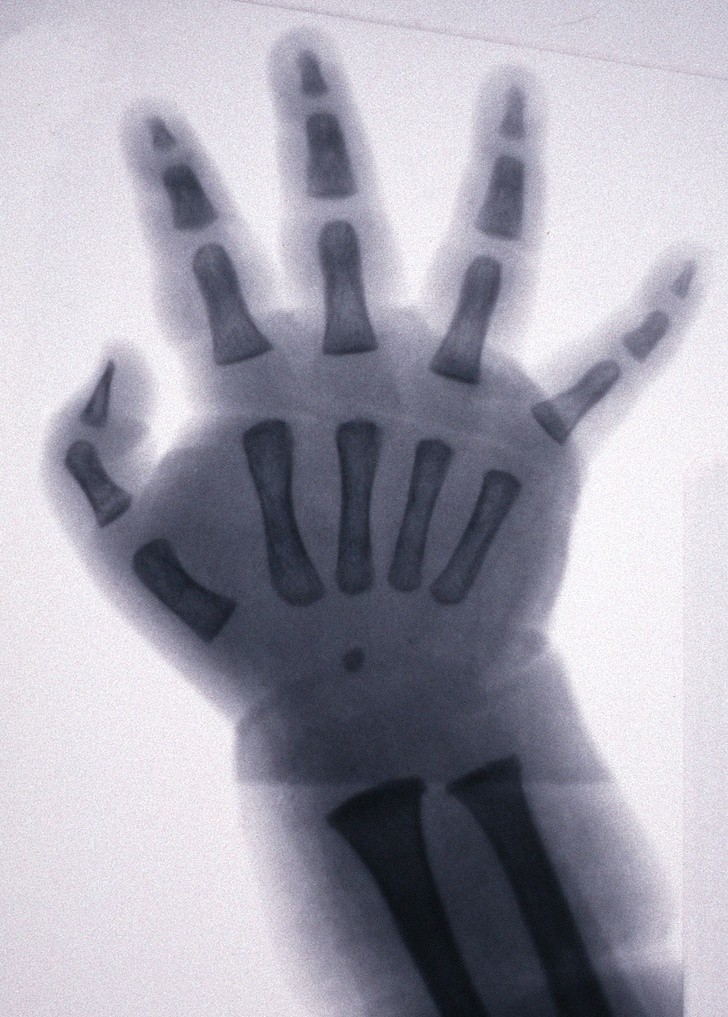

7. Prześwietlenie dłoni dziecka, która, w przeciwieństwie do osób dorosłych, posiada chrząstki zamiast kości

7. Prześwietlenie dłoni dziecka, która, w przeciwieństwie do osób dorosłych, posiada chrząstki zamiast kości © EAST NEWS